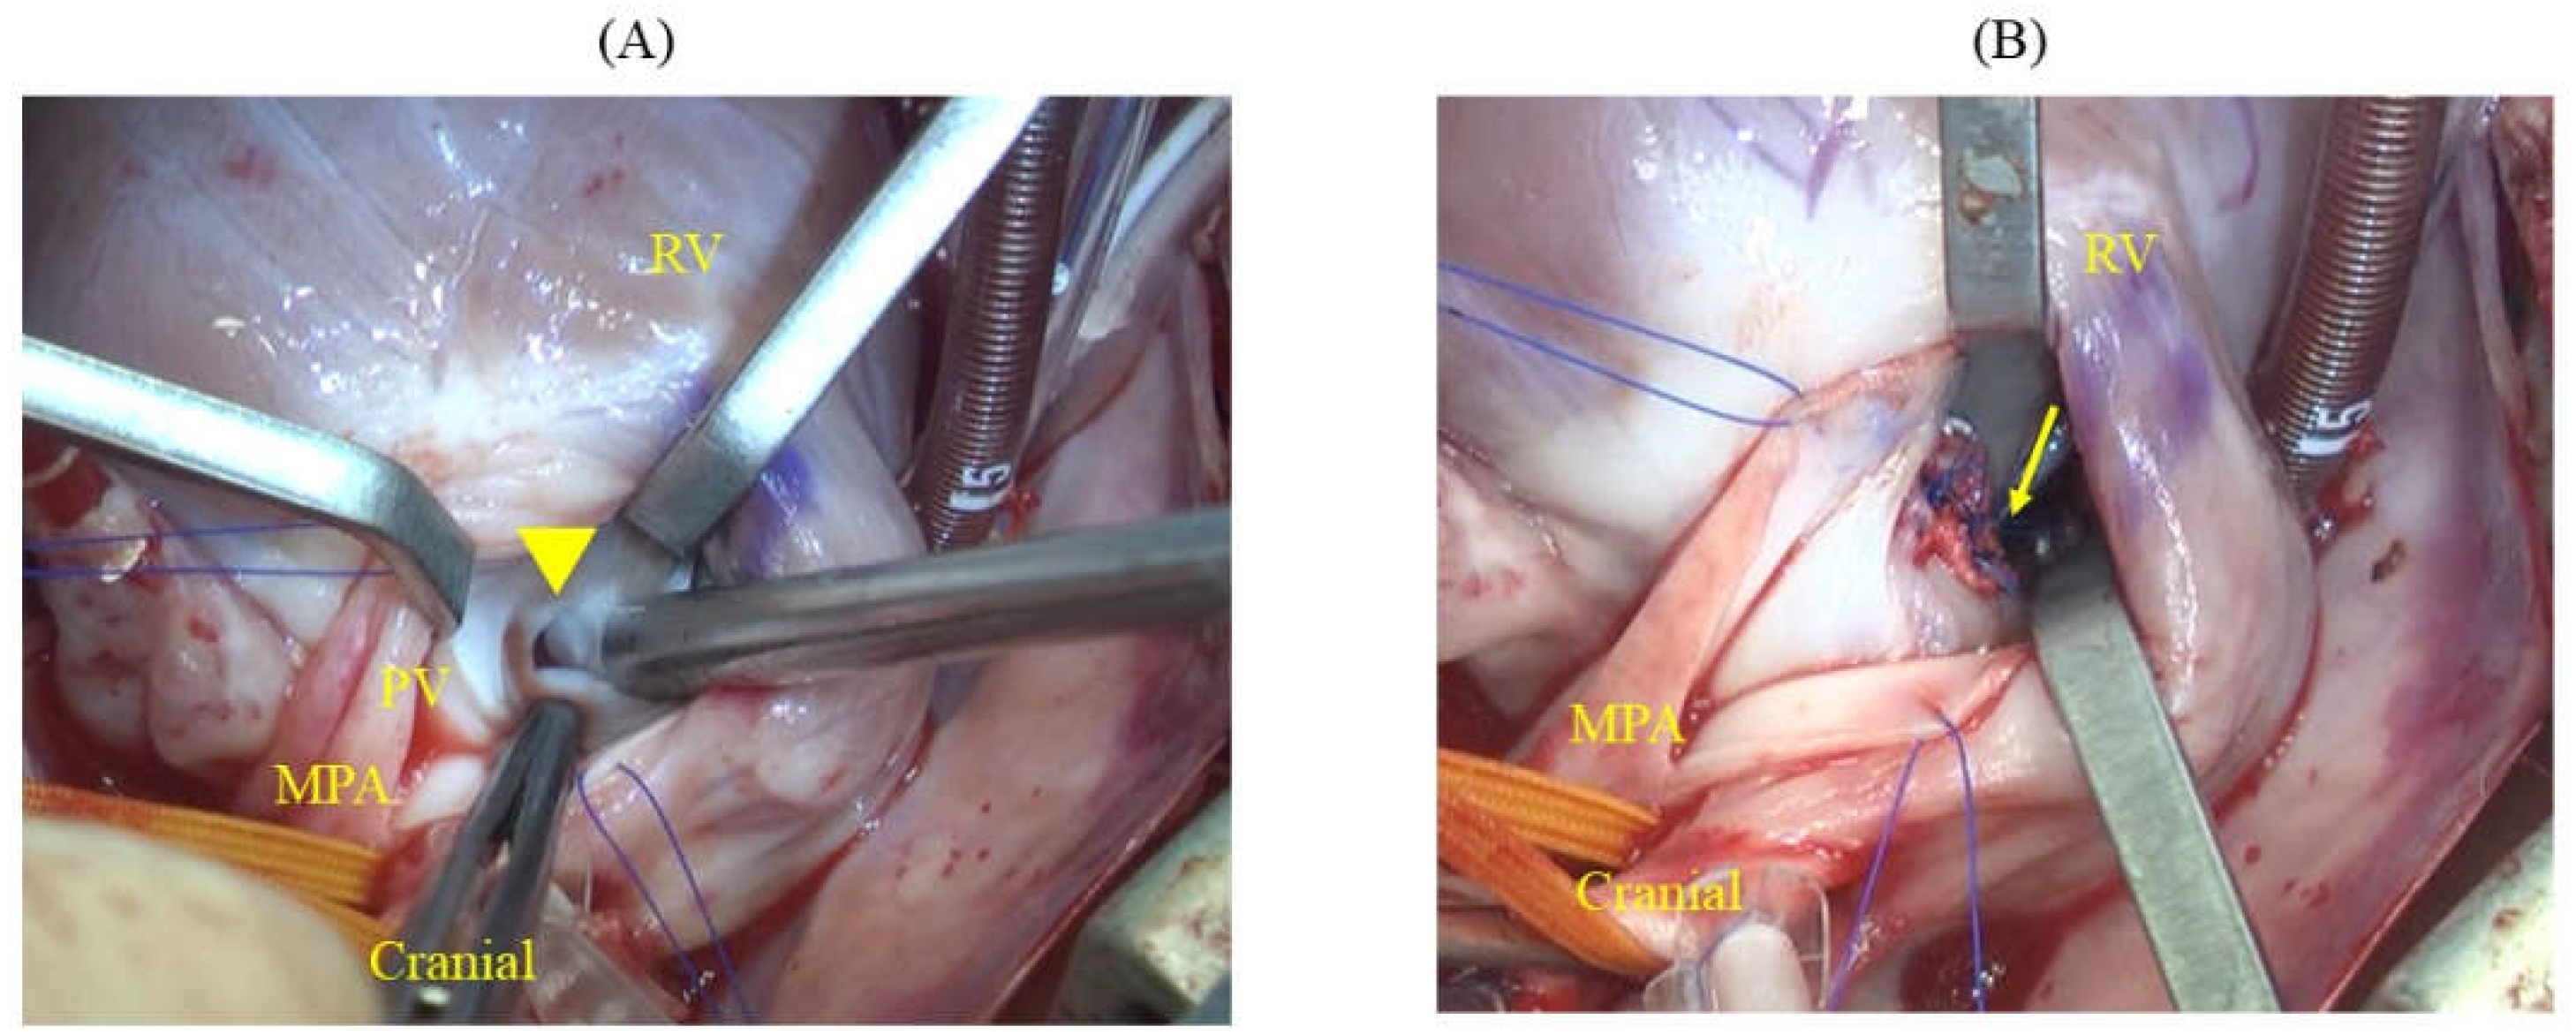

On day 383, the cat weighed 4.44 kg (BCS: 4/9). Echocardiography revealed that the VSD had a minor axis of 1.2 mm and major axis of 8.1 mm (Figure 1) with a VSD/Ao ratio of 95.3%. Color Doppler imaging in the right parasternal short-axis view at the level of the aortic valve revealed a shunt flow at the 12 o’clock position (Figure 1B). The LA/Ao ratio was 1.69 (1.43/0.85 cm; normal range < 1.5 [10]), which was considerably enlarged, and the left ventricular internal diameter in diastole (LVIDd) was 1.8 cm, at the upper limit of the normal range for an adult cat weighing 4.5 kg (1.8 cm, range: 1.27–1.98 cm [11]).

Figure 1. Echocardiographic findings. (A) Right parasternal long-axis view of the LV outflow tract showing a VSD directly below the aortic valve (yellow arrow-head). (B) Right parasternal short-axis view at the level of the aortic valve using color flow Doppler, where the largest diameter of the VSD is observed during diastole. The left-to-right shunt from the VSD is at 12 o’clock direction, located between the TV and pulmonary valve (yellow arrow). LA: left atrium; LV: left ventricle; Ao: aorta; RA: right atrium; TV: tricuspid valve; RV: right ventricle; VSD, ventricular septal defect.